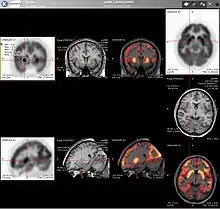

Neurology

PET imaging with oxygen-15 indirectly measures blood flow to the brain. In this method, increased radioactivity signal indicates increased blood flow which is assumed to correlate with increased brain activity. Because of its 2-minute half-life, oxygen-15 must be piped directly from a medical cyclotron for such uses, which is difficult.[17]

PET imaging with FDG takes advantage of the fact that the brain is normally a rapid user of glucose. Standard FDG PET of the brain measures regional glucose use and can be used in neuropathological diagnosis.

Brain pathologies such as Alzheimer's disease (AD) greatly decrease brain metabolism of both glucose and oxygen in tandem. Therefore FDG PET of the brain may also be used to successfully differentiate Alzheimer's disease from other dementing processes, and also to make early diagnoses of Alzheimer's disease. The advantage of FDG PET for these uses is its much wider availability. Some fluorine-18 based radioactive tracers used for Alzheimer's include florbetapir, flutemetamol, Pittsburgh compound B (PiB) and florbetaben, which are all used to detect amyloid-beta plaques, a potential biomarker for Alzheimer's in the brain.[18]

PET imaging with FDG can also be used for localization of "seizure focus". A seizure focus will appear as hypometabolic during an interictal scan.[19] Several radiotracers (i.e. radioligands) have been developed for PET that are ligands for specific neuroreceptor subtypes such as [11C]raclopride, [18F]fallypride and [18F]desmethoxyfallypride for dopamine D2/D3 receptors; [11C]McN5652 and [11C]DASB for serotonin transporters; [18F]mefway for serotonin 5HT1A receptors; and [18F]Nifene for nicotinic acetylcholine receptors or enzyme substrates (e.g. 6-FDOPA for the AADC enzyme). These agents permit the visualization of neuroreceptor pools in the context of a plurality of neuropsychiatric and neurologic illnesses.